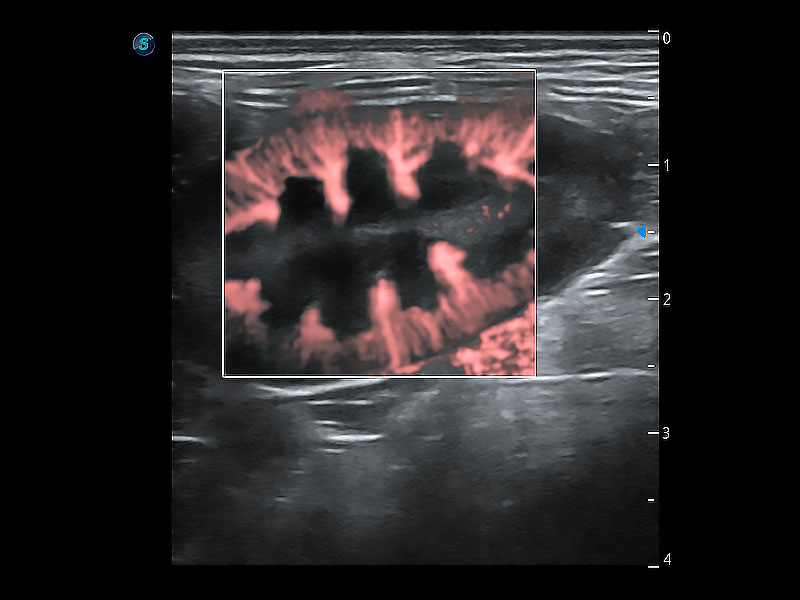

• Micro F 显微血流成像

极大提升超低速微细血流的检出能力,同时更精准地滤除软组织和超声信号,为兽用医生提供以往无法通过常规血流获得的疾病诊断信息。

(犬)肠道

(犬)肾脏显微血流